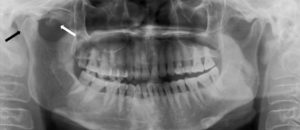

DefiniciónLa sinusitis maxilar de origen odontogénico o dental, también conocida como sinusitis crónica de maxilar de origen dental, o sinusitis maxilar odontogénica, es una enfermedad